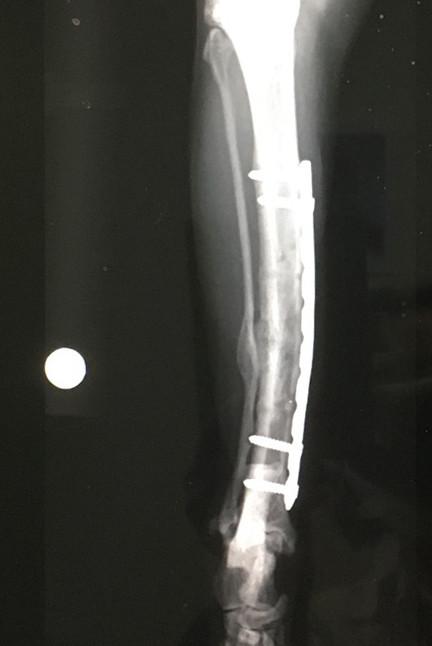

4月15日 手術から9ヶ月 後

札幌病院、経過観察、骨形成OK

6月3日 手術から 11ヶ月 後

7月に残りのプレート抜去予定

7月17日 手術から 12ヶ月 後

2回目のプレート抜去

メインプレートとボルト4本抜去。